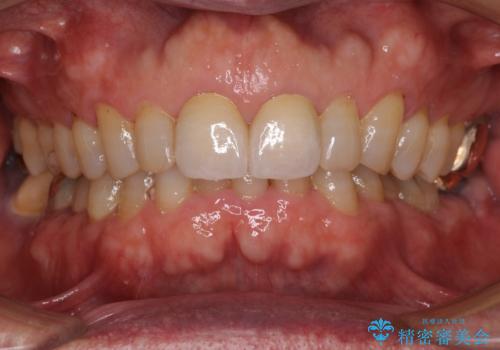

- 前歯のすきっ歯を気にして来院された患者様です。

矯正かオールセラミックか、治療の選択がありましたが、ご年齢や色の濃い点を考慮してオールセラミッククラウンにて補綴することとしました。

折角なのできれいに仕上げたいとのことで、オーダーメイドタイプのクラウンを選択されました。色調を周りのご自身の歯と合わせることができるため、自然な仕上がりをご希望の方におすすめです。